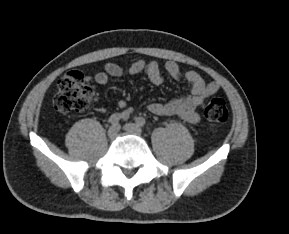

Компьютерная томография позволяет детально визуализировать структуру лимфатических узлов, выявить ее неоднородность, гиперплазию, определить деформацию контуров, появление инфильтрации окружающих тканей с образованием пакетов и конгломератов лимфоузлов.

В ходе сканирования врач оценивает структуру, размеры, плотность, контуры лимфатических узлов этих анатомических областей. Изменения этих параметров могут указывать на: